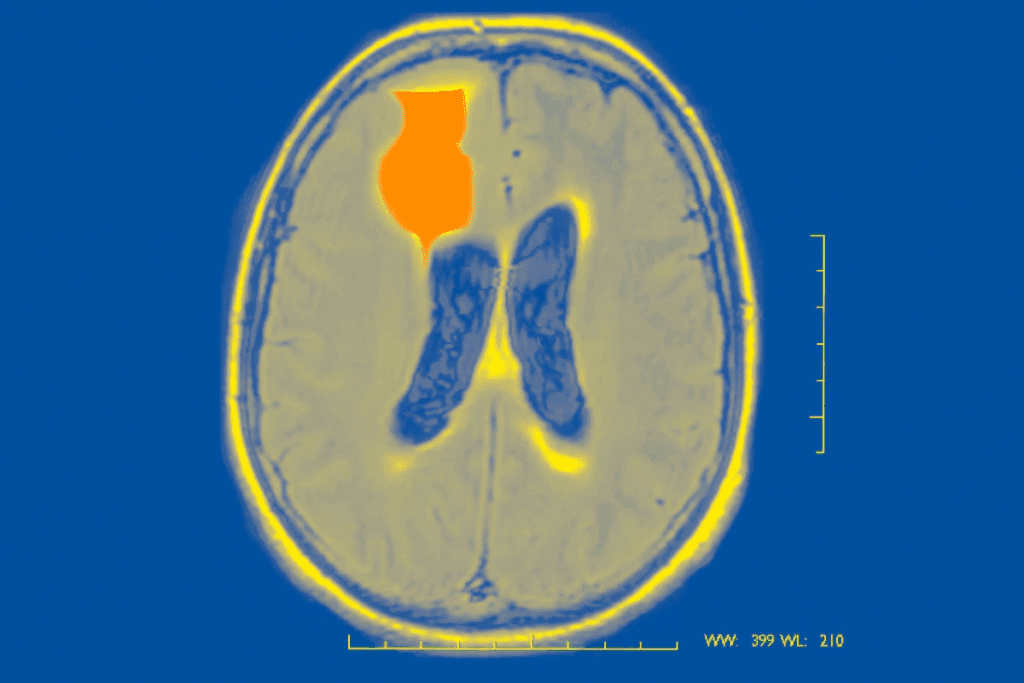

Do Seizures Cause Brain Damage? The Scientific Evidence

It’s important to know how seizures affect the brain. Research has shown both short-term and long-term effects. Seizures happen when the brain’s electrical activity goes wrong.

Research Findings on Seizure-Related Brain Changes

Many studies have looked into what happens in the brain after seizures. They found that seizures can change how the brain works and even its structure. This includes changes in electrical activity, neurotransmitters, and brain regions.